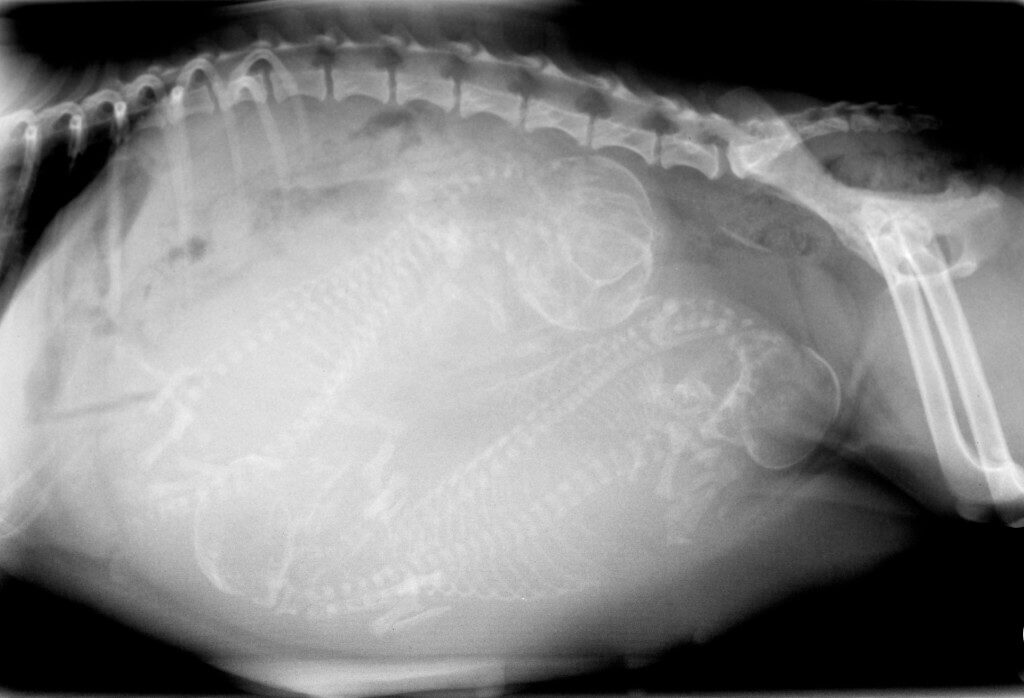

Our practice uses digital radiology both for dental purposes and for your pet’s whole body. Dental digital radiology allows our practice to view the internal anatomy of the teeth including the roots and surrounding bone. In the rest of your pet’s body, digital x-rays can help us identify a fractured bone, or degeneration in a joint as well as sometimes identify foreign objects inside your pet’s body. An added bonus to digital radiology is the fact that it emits less radiation than traditional radiology.